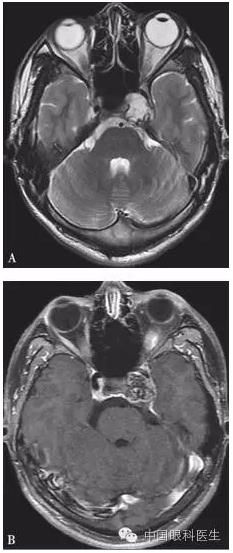

体格检查:双眼矫正视力0.8。右眼眼睑位置及眼球运动均正常,左眼上睑下垂,遮盖瞳孔上半部分,提上睑肌肌力4mm,左眼不能外展,上转、下转、内收运动均部分受限。患者右眼瞳孔直径3mm,左眼4mm;右眼对光反射灵敏,左眼迟钝,RAPD(-)。双眼眼底、眼压均正常。视觉诱发电位(visual evoked potential,VEP)、视野检查均未见明显异常。头颅MRI平扫+增强结果显示,左侧鞍旁海绵窦内T1WI稍低信号、T2WI稍高信号影,大小为21mm×23mm×22mm,增强扫描病灶呈不均匀强化,内可见多发的未强化区,左侧颈动脉海绵窦段受压外移,但结构未见明显损害(图2-3-0-1)。头颅CT平扫显示左侧鞍旁密度减低影,CT值为21Hu,大小为2.3cm,边缘可见钙化影,双侧眶内和球后未见异常(图2-3-0-2)。患者转入神经外科并行经额颞颧弓硬膜外入路左侧海绵窦区占位性病变切除术。术中快速冰冻切片病理学检查示,切除的组织标本富含黏液,制片困难。术后病理报告:左侧海绵窦区软骨源性肿瘤。考虑软骨瘤可能性大,局部细胞生长活跃,细胞间质伴黏液变性,免疫组织化学染色显示,肿瘤细胞对S-100和CK均呈阴性反应(图2-3-0-3)。术后患者左眼视力下降,额部及颊部皮肤感觉迟钝。眼科检查:右眼检查同术前,左眼矫正视力0.5,角膜上皮粗糙,角膜荧光素染色弥漫性着色,RAPD(-)。检眼镜检查示视盘界清,色红,视网膜血管走行正常,黄斑区未见明显异常。VEP、视野检查均未见明显异常。给予玻璃酸钠滴眼液点左眼、重组牛碱性成纤维细胞生长因子软膏涂左眼结膜囊并给予营养神经、改善全身血液循环药物治疗1周后,检查示见角膜上皮透明,角膜荧光素染色不明显,矫正视力0.8,左眼提上睑肌肌力测试可上提10mm。术后1个月复诊见,上睑下垂治愈,眼球运动受限明显好转。

注:A. T2WI;B.增强扫描。左侧鞍旁海绵窦内可见T1WI稍低信号、T2WI稍高信号影,大小约为21mm×23mm×22mm,增强扫描病灶呈不均匀强化,其内可见多发未强化区,左侧颈动脉海绵窦段受压外移,未见明显侵犯